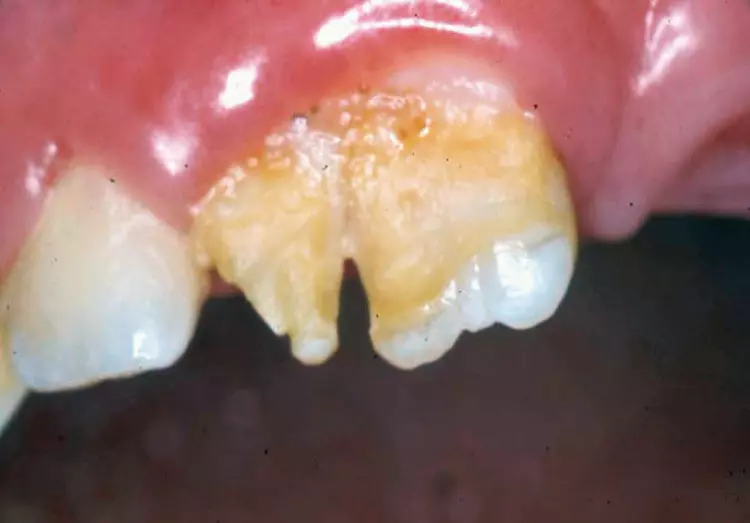

Wie bei der bleibenden Dentition stellen die Intrusionen ein besonderes Problem dar: Bei 4 bis 22% der Traumata im Milchgebiss bei sehr kleinen Kindern im Alter von 1 bis 3 Jahren [15] resultiert eine relevante Schädigung des Zahnkeimes und damit nachfolgenden Zahnes [16] wie Schmelzhypoplasien, Kronenverlagerungen, odontomähnliche Verformungen, Kronen-/Wurzelabknickung, Einstellung der Wurzelbildung, Infektion des Zahnkeimes und Schmelzschädigung sowie Durchbruchsstörungen beim bleibenden Zahn (Abb. 6a u. b).

Prinzipiell steht bei der Intrusion die abwartende Therapie mit der Möglichkeit einer spontanen Reeruption innerhalb weniger Wochen der zügigen Entfernung gegenüber, die den Druck auf den bleibenden Zahn sofort mindert, aber oft nicht ohne Narkose erfolgen kann. Randomisierte und damit hochwertige Vergleichsstudien existieren nicht und somit kann nur anhand von biologischer Plausibilität geraten werden, bei unkomplizierten Fällen primär der Reeruption eine Chance zu geben. Die Empfehlung, intrudierte Milchzähne reeruptieren zu lassen, basiert auf der bukkalen Position der Intrusion zum Zahnkeim (siehe Abb. 5).